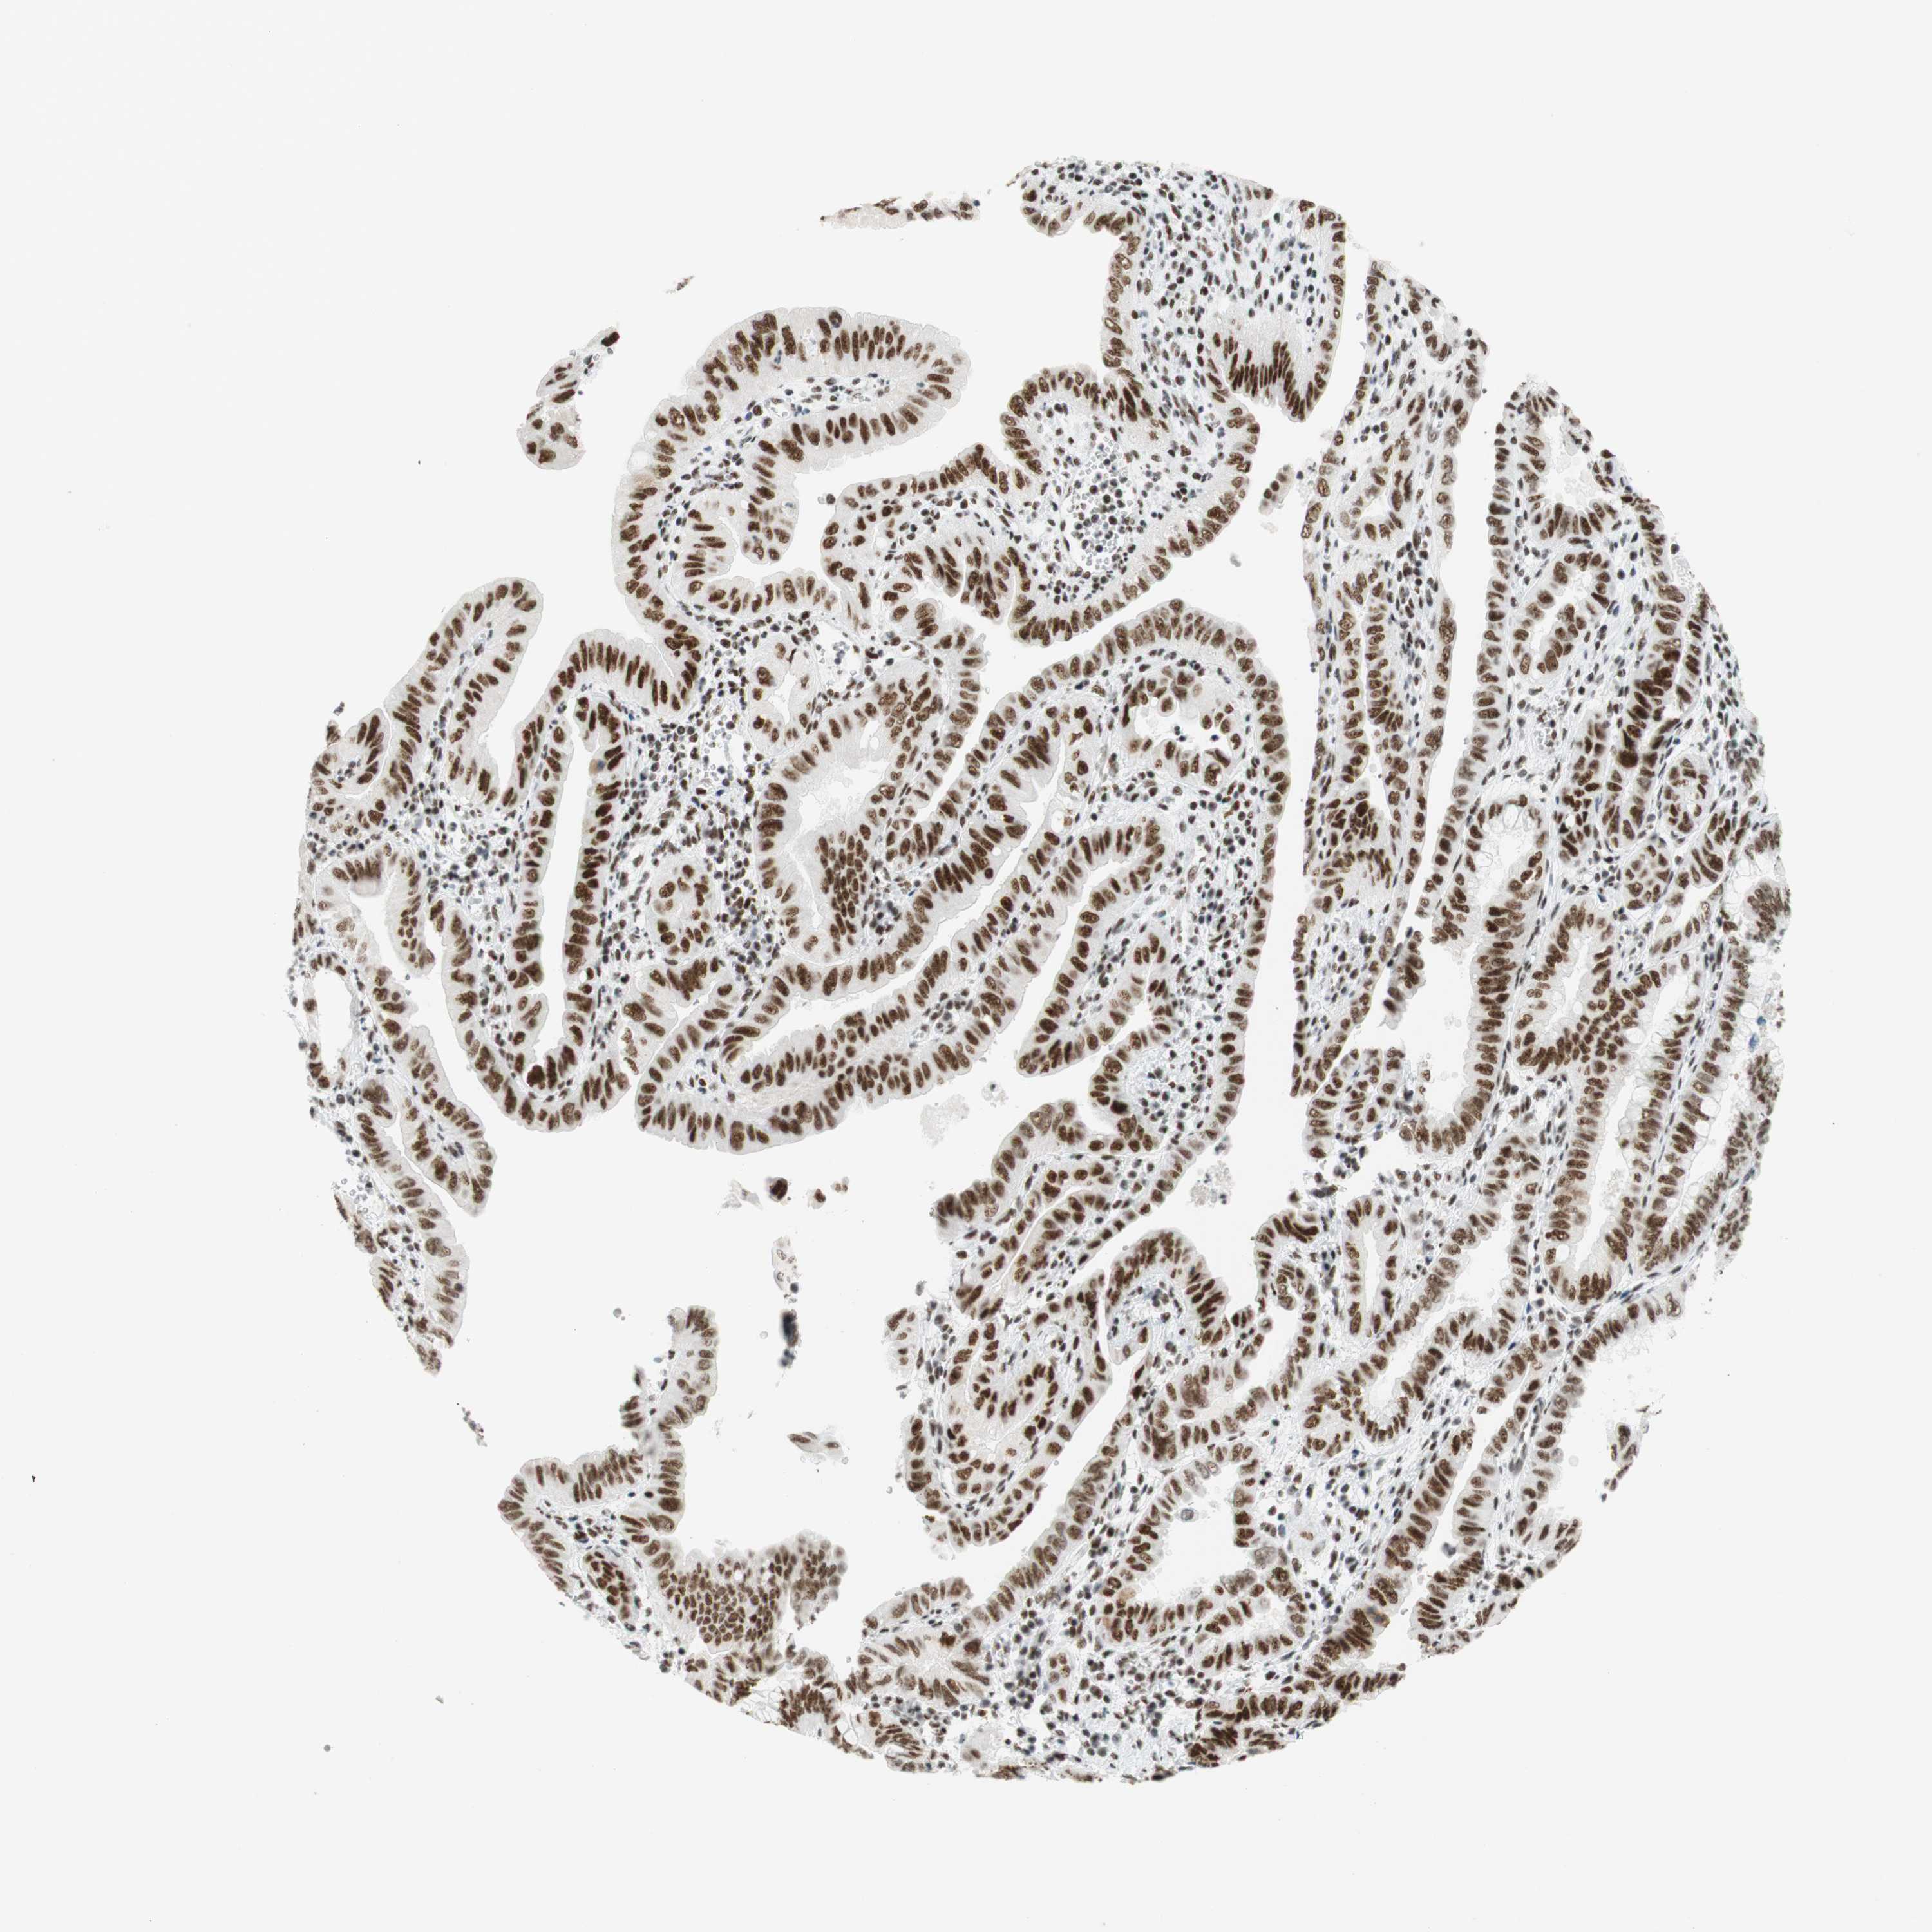

PANCREATIC CANCER - Protein expressioni

A mouse-over function shows sample information and annotation data. Click on an image to view it in a full screen mode. Samples can be filtered based on level of antibody staining by selecting one or several of the following categories: high, medium, low and not detected. The assay and annotation is described here.

Note that samples used for immunohistochemistry by the Human Protein Atlas do not correspond to samples in the TCGA dataset.

Antibody stainingi

Antibody staining in the annotated cell types in the current human tissue is reported as not detected, low, medium, or high, based on conventional immunohistochemistry profiling in selected tissues. This score is based on the combination of the staining intensity and fraction of stained cells.

Each image is clickable and will lead to virtual microscopy that enables deeper exploration of all samples and also displays staining intensity scores, fraction scores and subcellular localization as well as patient and tissue information for each sample.

Antibody CAB012478

Staining

High

Medium

Low

Not detected

Intensity

Strong

Moderate

Weak

Negative

Quantity

>75%

75%-25%

<25%

None

Location

Nuclear

Cytoplasmic/membranous

Cytoplasmic/membranous,nuclear

Adenocarcinoma, NOS

Adenocarcinoma, metastatic, NOS